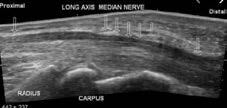

Carpal Tunnel Syndrome is a common occupational injury and can occur from lifting, typing and repetitive strain. It is caused by pressure on the median nerve.

Carpal Tunnel Syndrome is a repetitive trauma and compression of the median nerve in the wrist. This can be caused by lifting, typing or repetitive bending and straightening of the fingers and thumb.